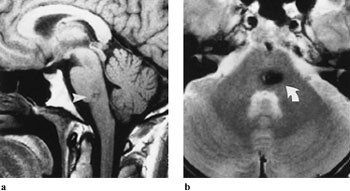

Fasikulær lesjon i hjernestammen er hyppig, og alltid assosiert med andre utfall, som hemiparese, hemitremor eller cerebellar ataksi, avhengig av hvilke andre strukturer som skades samtidig (tab 2) (1). Påvisning av patologisk tilstand, både ved kjerneområdet og i hjernestammen, som kan være betinget i blødning, infarkt, tumor, demyelinisering eller arteriovenøs malformasjon, gjøres best med MR (2), (fig 1a, b). Hjernestammen fremstilles dårlig med CT pga. artefakter fra omgivende bein, og CT bør kun anvendes i tilfeller hvor MR-undersøkelse er kontraindisert (pacemaker, ikke magnetkompatible klips, klaustrofobi). Oculomotoriusnerven i cisternerommet kan påvirkes av aneurisme (a. carotis interna eller a. communicans posterior). Dette er årsaken til parese i hjernenerve III hos en tredel av pasientene (3), og hos de aller fleste starter det med kraftig hodepine. Dilatasjon av pupillen er i slike tilfeller nesten obligatorisk funn, siden pupillens motorfibrer er beliggende overflatisk i nerven i dette området og er meget vulnerable for trykk. I mindre enn 5 % av tilfellene er pupillen ikke affisert. Man kan ikke utelukke aneurisme selv om hodepinen mangler. Aneurismer kan debutere med subaraknoidalblødning. CT uten kontrast er den beste metoden for å vise blod i subaraknoidalrommet (4). CT-angiografi er vårt første valg for å fremstille aneurismer (fig 2a, b), men metoden krever injeksjon av kontrastmiddel (5). Ved sterk klinisk mistanke og negativ CT-angiografi bør konvensjonell angiografi utføres.

Langsomt progredierende oculomotoriusparese med pupillaffeksjon kan være forårsaket av nevrinom, som er isointens på T1- og T2-vektede MR-bilder og viser kraftig signalopptak etter intravenøs injeksjon av gadoliniumkontrast (fig 3).